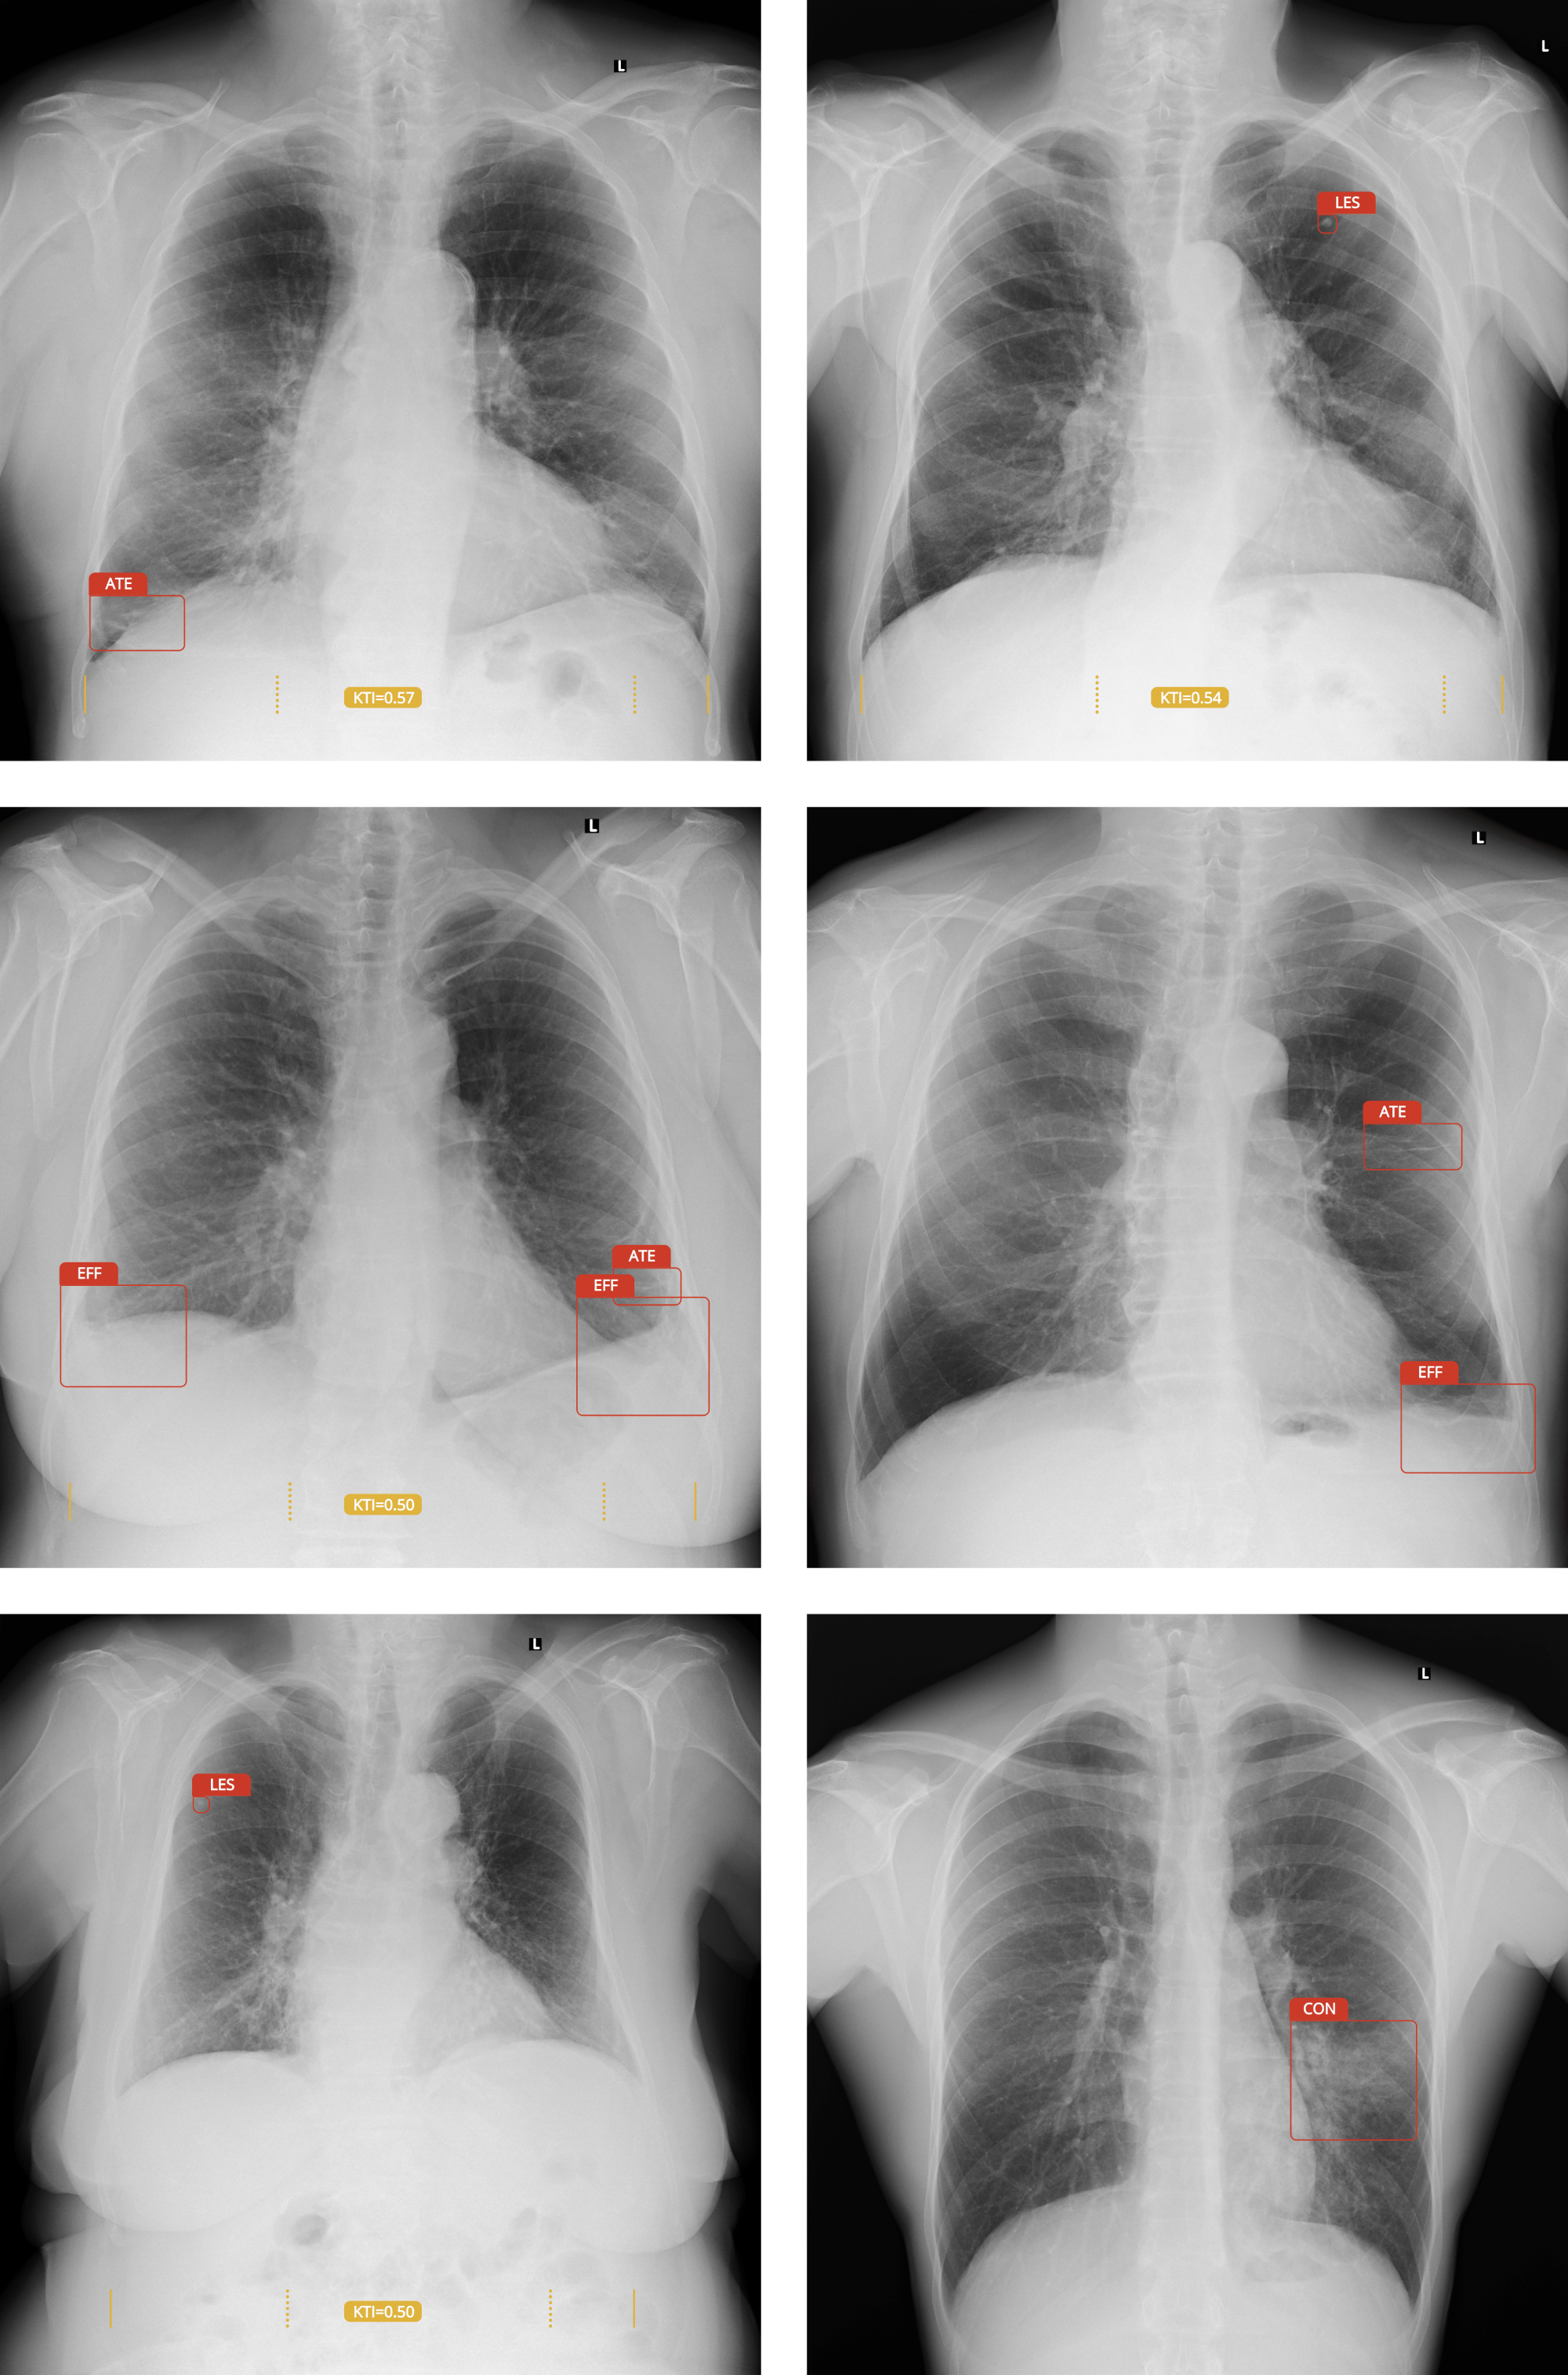

Dodává sebevědomí při vyhodnocování snímků a vizuálně upozorní na nálezy. Lékař je ten, který potvrzuje nálezy a určuje diagnózu. Snižuje pracovní vytížení, šetří čas a může snížit počet chybných diagnóz.

"Pokud by běžný snímek hrudníku u pacienta s rakovinou plic vyhodnotila umělá inteligence, lézi by bylo možné identifikovat dříve, což by mohlo zachránit pacientovi život.“